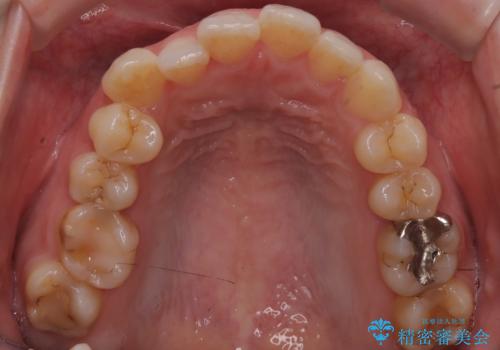

- 歯並びの乱れを改善したいと来院されました。精密検査の結果、犬歯を奥へ動かすことで、より美しい口元と安定した咬み合わせが得られると診断。患者様のご希望から、目立ちにくい審美ワイヤー矯正を採用し、効率的な歯の移動のために**リンガルアーチとTAD(矯正用アンカースクリュー)**を併用する計画を立てました。これにより、抜歯せずにスペースを確保し、犬歯をスムーズに遠心へ移動させます。

今回の矯正では、装置が目立たないよう透明なブラケットと白いワイヤーを使用。さらに、効率的な歯の移動のために、歯の裏側にリンガルアーチを設置しました。また、確実な奥歯の移動のために**TAD(矯正用アンカースクリュー)**を一時的に使用。これにより、犬歯を狙った位置へ正確に動かすことが可能に。目立ちにくい装置で快適に過ごしながら、理想的な歯並びと咬み合わせを獲得していただけました。